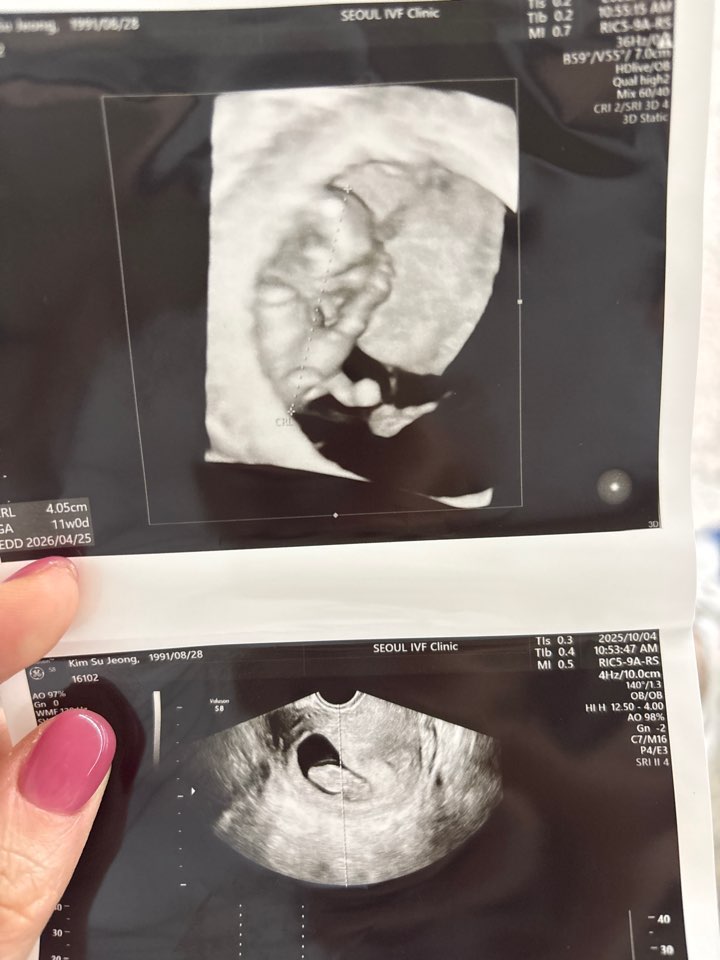

| 가슴 떨리는 임신 이야기를 공유해 주세요. | 채취를 하고 마지막배아가 남았었어요. 신선 동결1차 모두실패하고 마지막 이식날, 제일 마음을 편하게 먹었던 것 같아요. 안되면 다시 채취하면되지~!라는 마음으로 이식을 했고, 이번 이식은 출근도 안하고 집에서 정말 편히 쉬었어요. 5일부터 임테기 두줄을 보고 떨리는 마음으로 피검사를 갔고 좋은 결과를 들었습니다. |

| 서울IVF여성의원의 난임 치료에 대해 말씀해 주실 것이 있나요? | 이경훈 원장님께서 방향을 잘 잡아주시고 “하라는 대로만 해보자”는 안정감을 주셔서 믿고 따라갈 수 있었어요. 약·주사·식단까지 세심하게 맞춰주셔서 마음 놓고 치료에 집중할 수 있었습니다. 그리고 무엇보다 잘될거라는 마음이 젤 중요한 것 같아요~! |